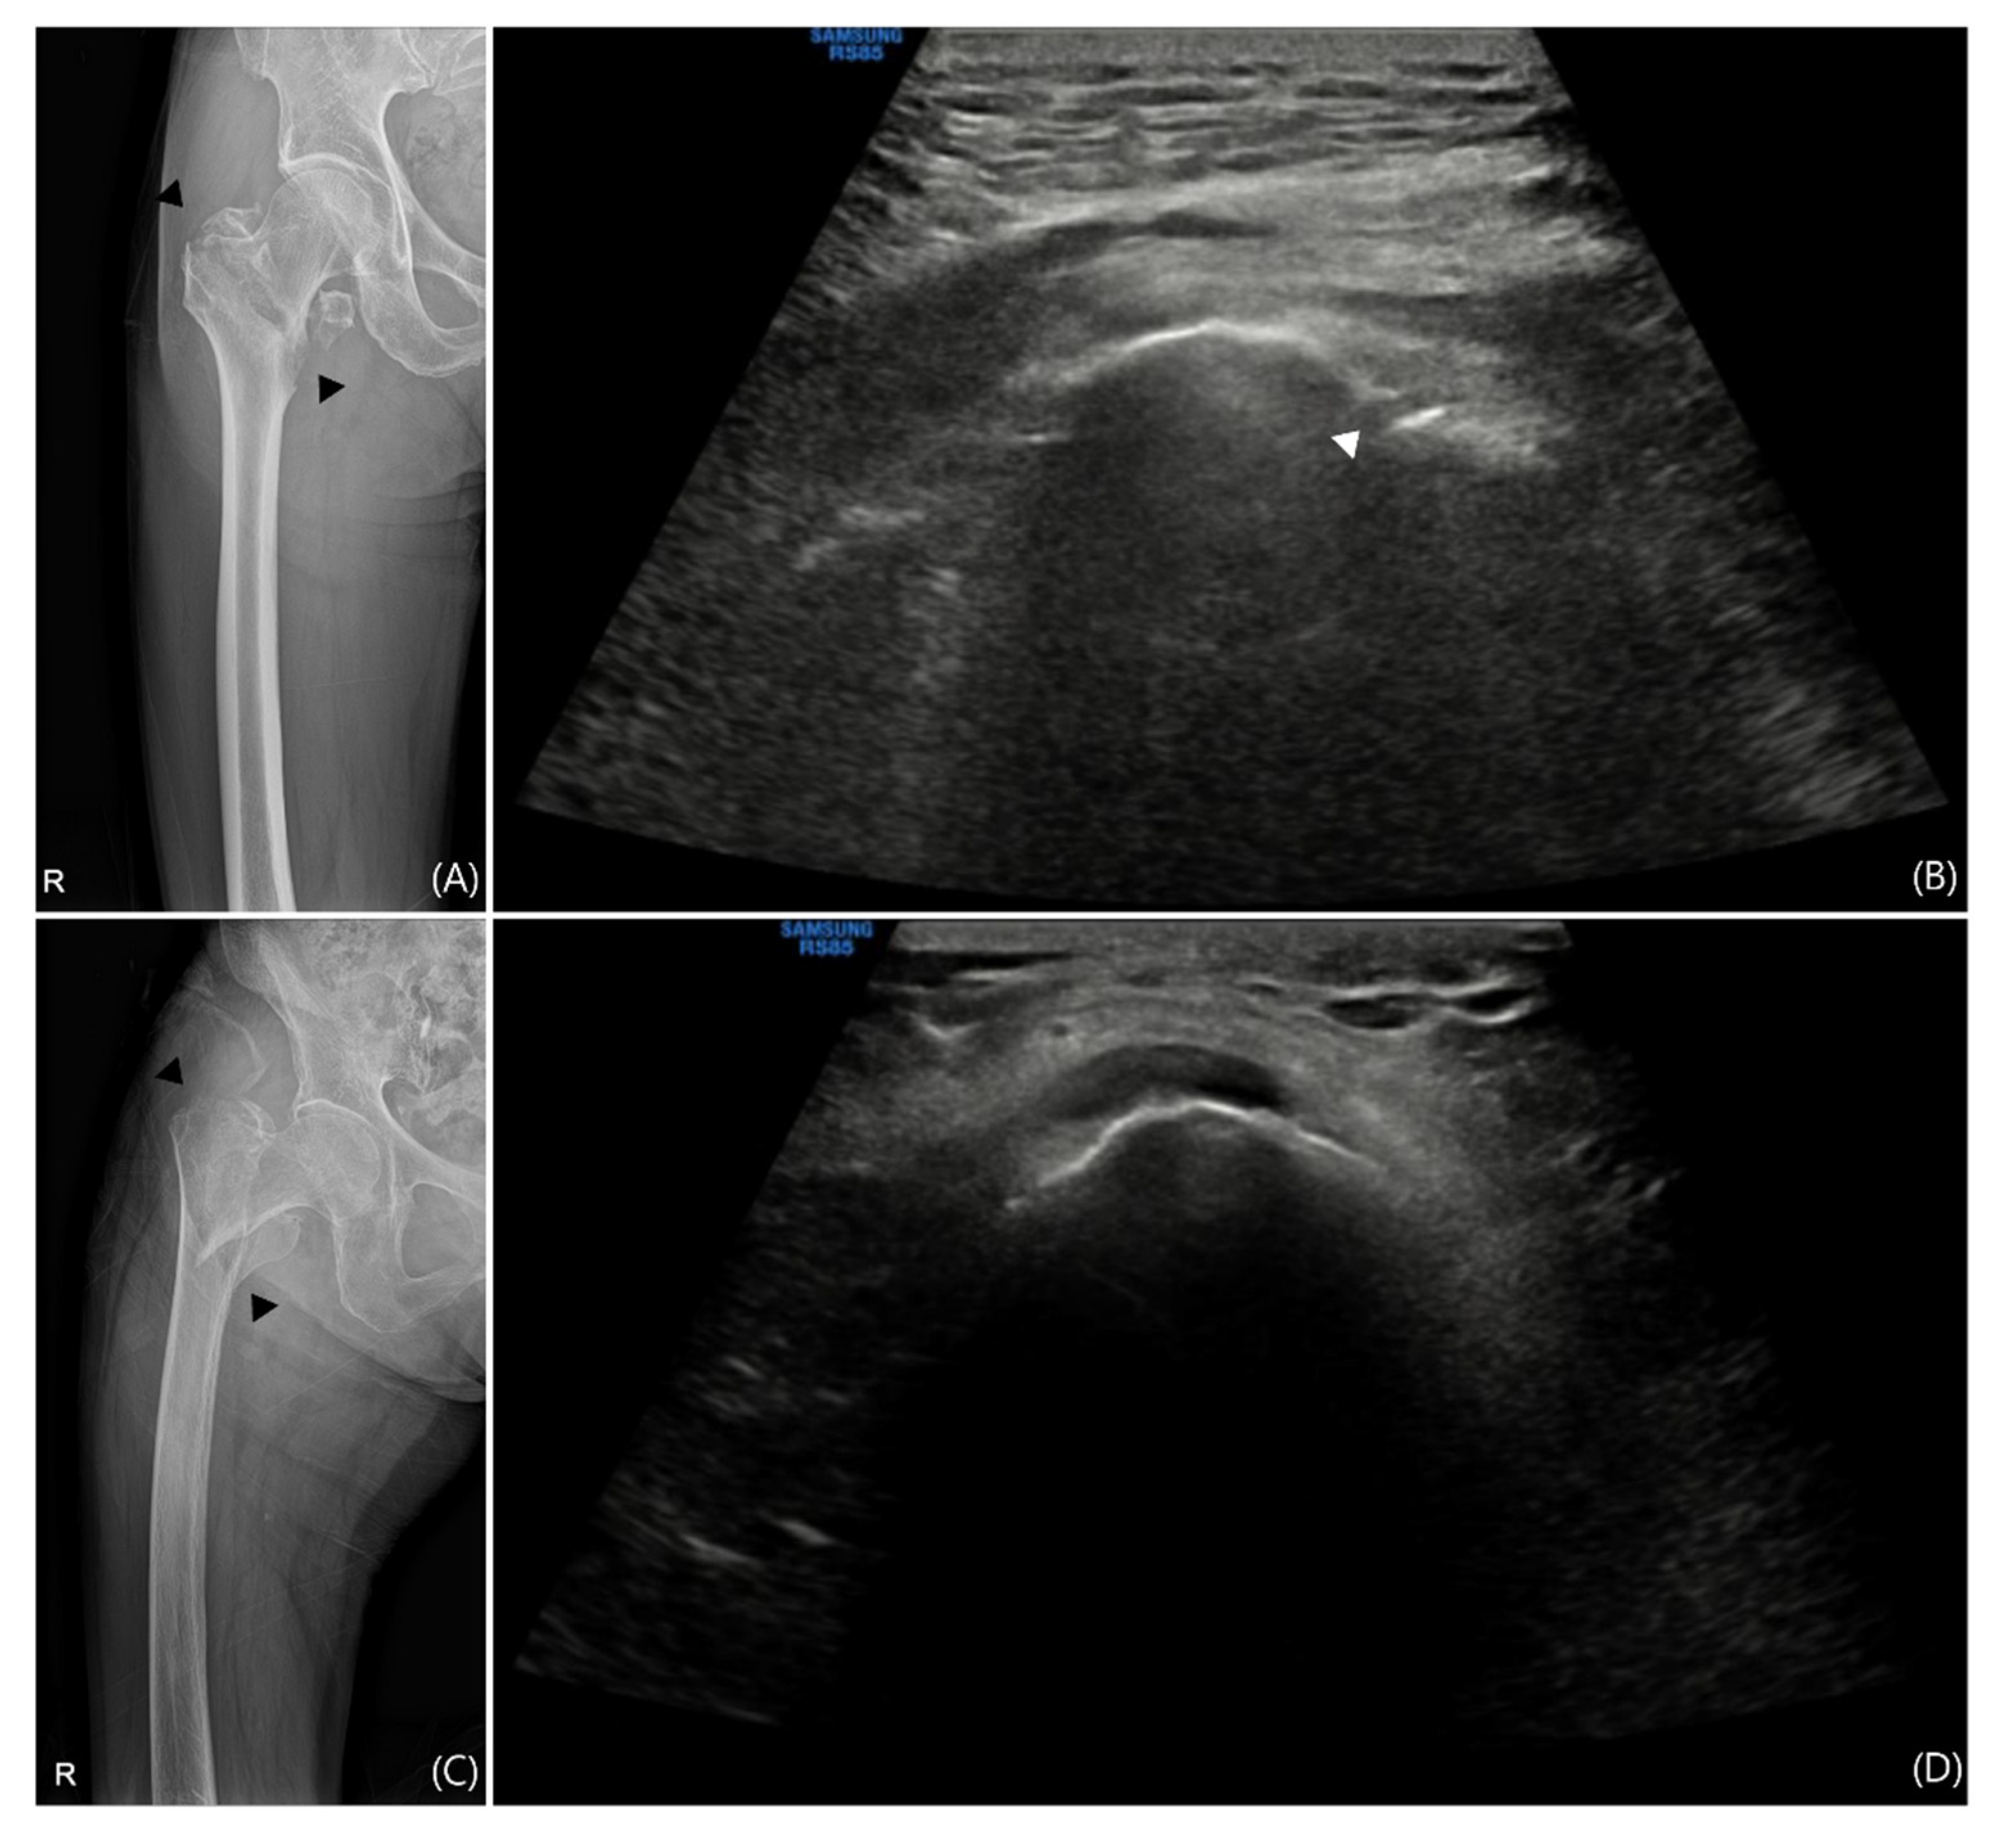

- Cocco, G.; Ricci, V.; Villani, M.; Delli Pizzi, A.; Izzi, J.; Mastandrea, M.; Boccatonda, A.; Naňka, O.; Corvino, A.; Caulo, M.; et al. Ultrasound imaging of bone fractures. Insights Imaging 2022, 13, 189. [Google Scholar] [CrossRef] [PubMed]

| Fracture | 0 (0%) | 48 (79%) |

| Fracture | 7 (11%) | 47 (77%) |